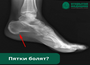

Пятки болят?

Рассказываем подробнее